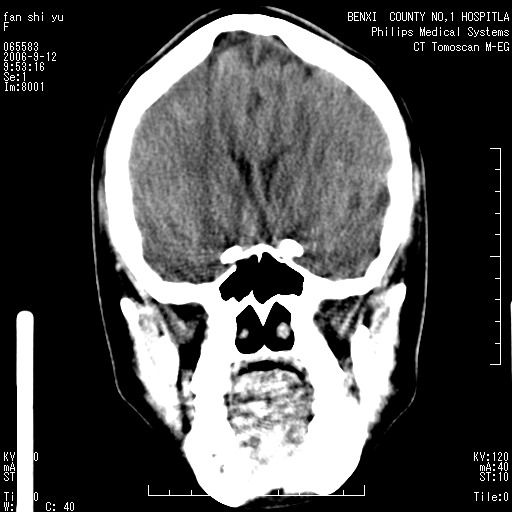

标题: CT4607:看看这个头颅冠状位。

女,22岁,自觉头顶部质硬包块.

巨大蛛网膜粒压迹。

巨大蛛网膜粒压迹